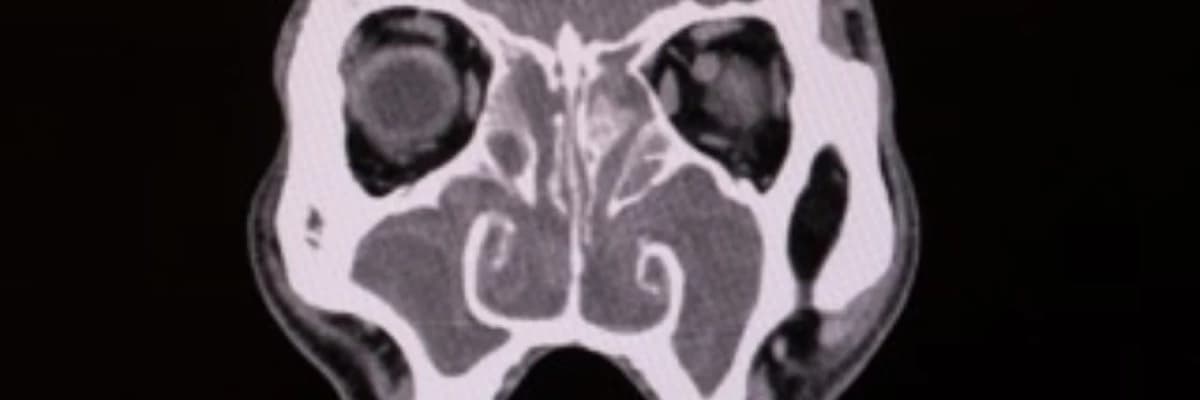

Tıbbi literatür verilerine göre, gribal enfeksiyonlar sırasında çekilen tomografilerde (BT) sinüslerde geçici anormallikler görülebilir ancak bunlar 2-3 haftada kendiliğinden düzelir.

Eğer şikayetleriniz 12 haftayı geçtiyse, uzman bir KBB hekimi şu yöntemlerle kesin teşhisi koyar:

- Endoskopi: Burun içindeki iltihaplanmanın ya da polip oluşumlarının doğrudan görülmesi.

- BT (Tomografi): Sinüslerdeki kronik tıkanıklığın ve olası poliplerin tespiti.